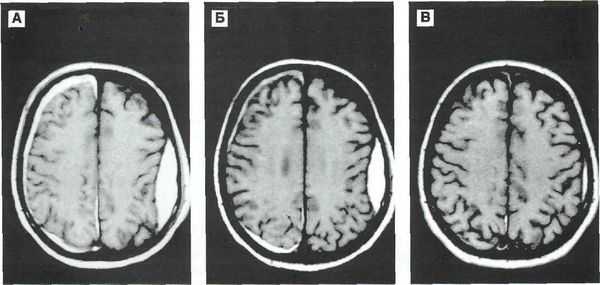

- Бесконтрастная компьютерная томография (КТ) — достоверный способ диагностики острых гематом головного мозга. КТ позволяет распознать гематому, её объём, воздействие на различные структуры головного мозга. На основании снимков КТ нейрохирург определяет тактику и объём оперативного вмешательства. Большинство стационаров, особенно оказывающих экстренную помощь, оснащены КТ аппаратами. Однако в хронической стадии и при пороках сосудов головного мозга без кровоизлияния КТ может не предоставить врачу нужной информации. В этих случаях применяют МРТ [8] .

- Магнитно-резонансная томография (МРТ) позволяет более подробно рассмотреть мягкотканные структуры. Поэтому в случае затруднений при диагностике, несмотря на проведённое КТ исследование, врач может назначить МРТ.